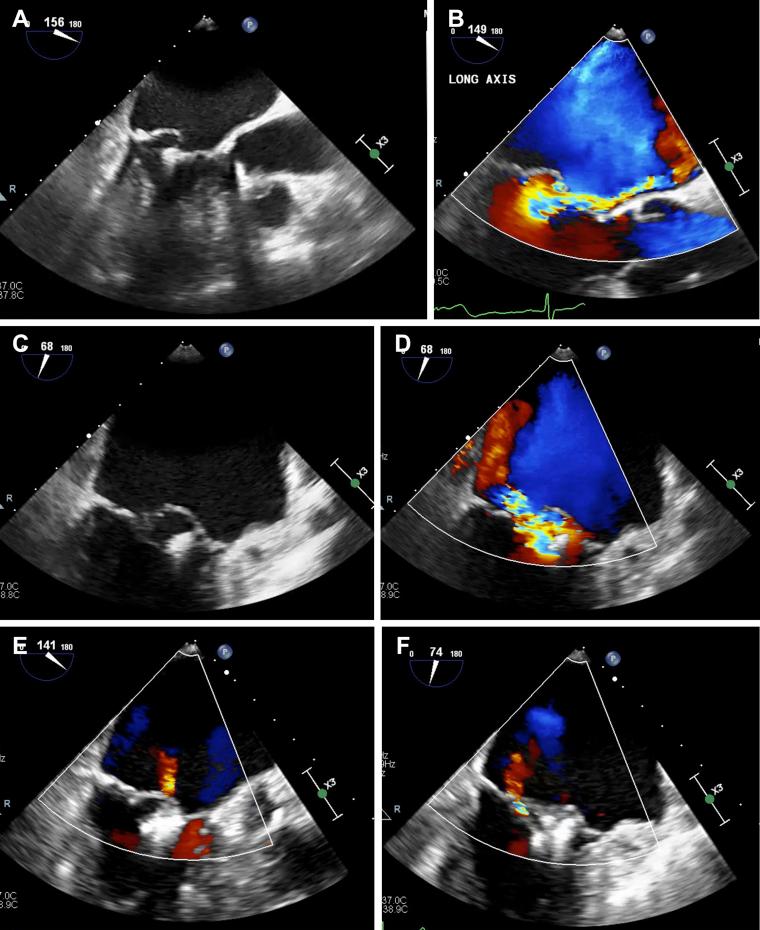

Transcatheter mitral valve repair using the MitraClip (Abbott Vascular, Santa Clara, CA) is a reasonable option for the treatment of patients with severe symptomatic degenerative mitral regurgitation (MR) who are at prohibitive surgical risk. The occurrence of recurrent severe MR after initial successful MitraClip repair is uncommon. Data are sparse on the management of recurrent severe MR after initial successful repair using the MitraClip. We describe a successful case of redo MitraClip repair for late recurrent severe MR secondary to progressive degenerative mitral valve disease after a successful initial MitraClip procedure and review the literature.